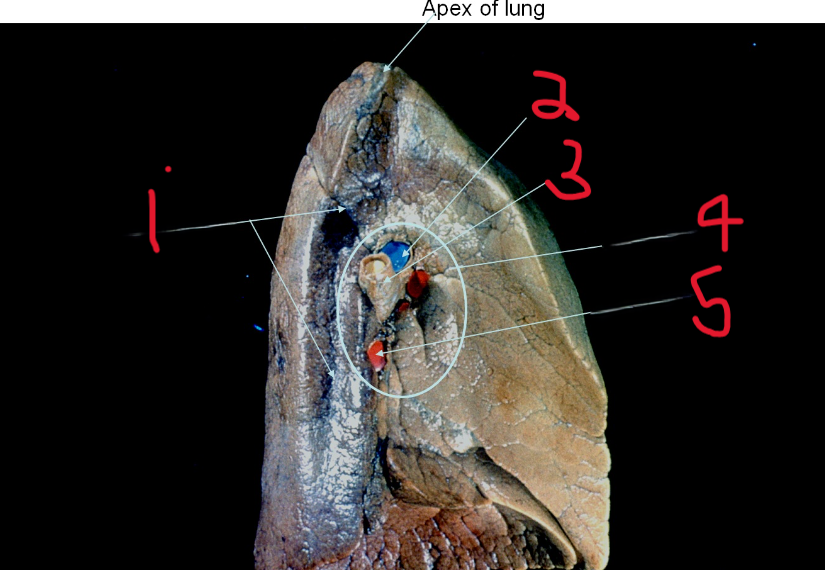

What is depicted by #1

Pulmonary artery

What is depicted by #2

Left main bronchus

What is depicted by #3

Hilum of lung

What is depicted by #4

Pulmonary vein

What is depicted by #5